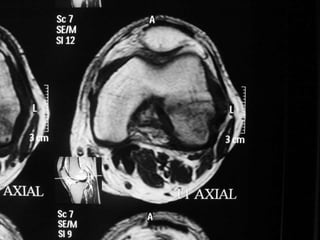

The document presents a detailed case study of a patient with transient osteoporosis of the hip (TOH) and spontaneous osteonecrosis of the knee (SONK) treated at Choithram Hospital & Research Centre in India. Over 20 years, the patient experienced multiple episodes of TOH and SONK with no history of trauma or co-morbidities, resulting in resolutions and recurrences of conditions. The information is intended for orthopedic surgery students and highlights personal experiences and case collections, with a disclaimer regarding content usage and potential controversies.